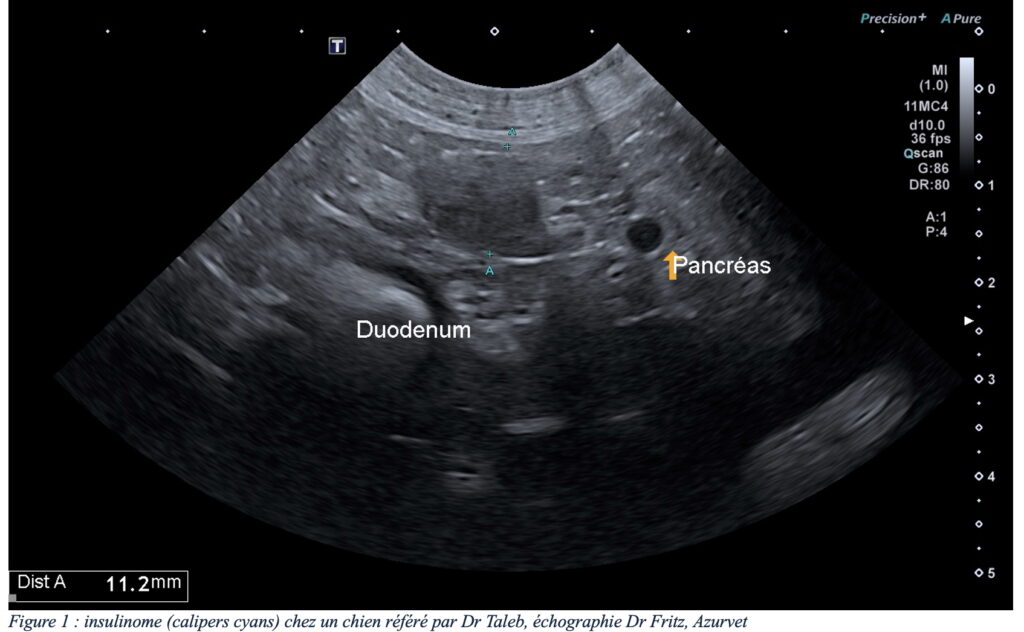

De l’expérience à Azurvet, certains animaux ont connu une première prise en charge chirurgicale couronnée de succès avec retour à une activité normale de l’animal. Certains de ces animaux ont même connu une récurrence des symptômes plusieurs mois après la chirurgie initiale, les examens d’imagerie ont ensuite mis en évidence un développement de récidive locale (figure 6) ou développement de métastases ganglionnaires et/ou hépatiques résécables (figure 7) permettant une seconde intervention, augmentant considérablement l’espérance de vie avec un confort satisfaisant.